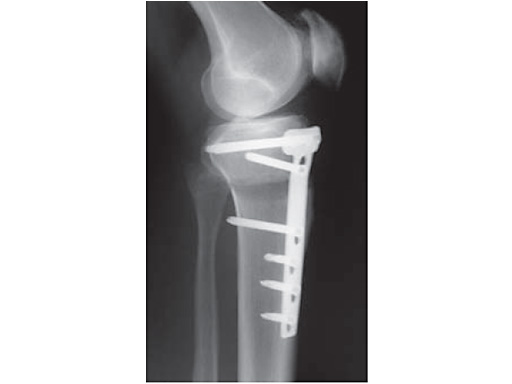

A 68-year-old female.

Case provided by Alex Staubli, Luzern, CH

The correction is planned on a long-leg standing x-ray. After surgery, the mechanical axis should pass through a point 63% on the lateral side of the total width of the tibial plateau in the frontal plane. A transverse or slightly oblique incision is used to avoid damage to the saphenous nerve. The distal fibers of the medial collateral ligament are detached from the tibia. Under fluoroscopic control, two wires are placed in the proximal tibia marking the transverse osteotomy plane. The cut usually starts at the upper margin of the pes anserinus and ends at the tip of the fibula on the lateral side. The wires are placed exactly parallel to the tibial plateau thus taking into consideration the individual tibial slope of the patient. An incomplete cut of the posterior two-thirds of the proximal tibia is performed with an oscillating saw guided by the wires. Continuous irrigation avoids burn injury to the bone. A second osteotomy is now performed in the anterior third of the tibia in an angle of 100 ending above the patellar tendon insertion. A smaller saw blade is used and the complete anterior cortex is cut exactly in the frontal plane. The osteotomy is now gradually opened by inserting flat chisels or a spreader-chisel into the posterior osteotomy cleft. This process may take some minutes and can usually be completed without fracture of the lateral cortex. A bone spreader is now placed in the posteromedial edge of the tibia and the chisels are removed. The leg is extended and the correction is checked with the fluoroscope. A long metal rod is placed between center of the hip joint and center of the ankle joint. The projection of this rod should be at the planned point of correction on the tibial plateau lateral of the midline. Eccentric collapse of the medial joint space may cause accidental overcorrection. In this case pressure on the foot may simulate loading and body weight. The correction can be fine-tuned by opening or closing the spreader. The TomoFix Medial Tibia Plate is now placed in a subcutaneous pocket. The implant is precontoured and usually fits well to the bone surface. The distance holders avoid compression of the medial collateral ligament and the pes anserinus. Three proximal bolts are placed near the subchondral sclerosis zone. The position of the bolts is adapted to the anatomy of the proximal tibia giving optimum purchase for the bolts. An oblique lag screw is inserted distal to the osteotomy. This screw in the first combination hole allows careful compression of the lateral osteotomy hinge and pretensioning of the implant. A stab incision is created on the shaft and the implant is fixed monocortically with bolts. The lag screw and the distance holders are replaced by bolts. The medial collateral ligament is released longitudinally to reduce medial compartment pressure and the wound is closed in layers. An overflow drain may be used. Clinical and experimental work has proven that when this technique is closely followed, corrections up to and over 15 mm can be performed without bone grafting or use of bone substitutes.